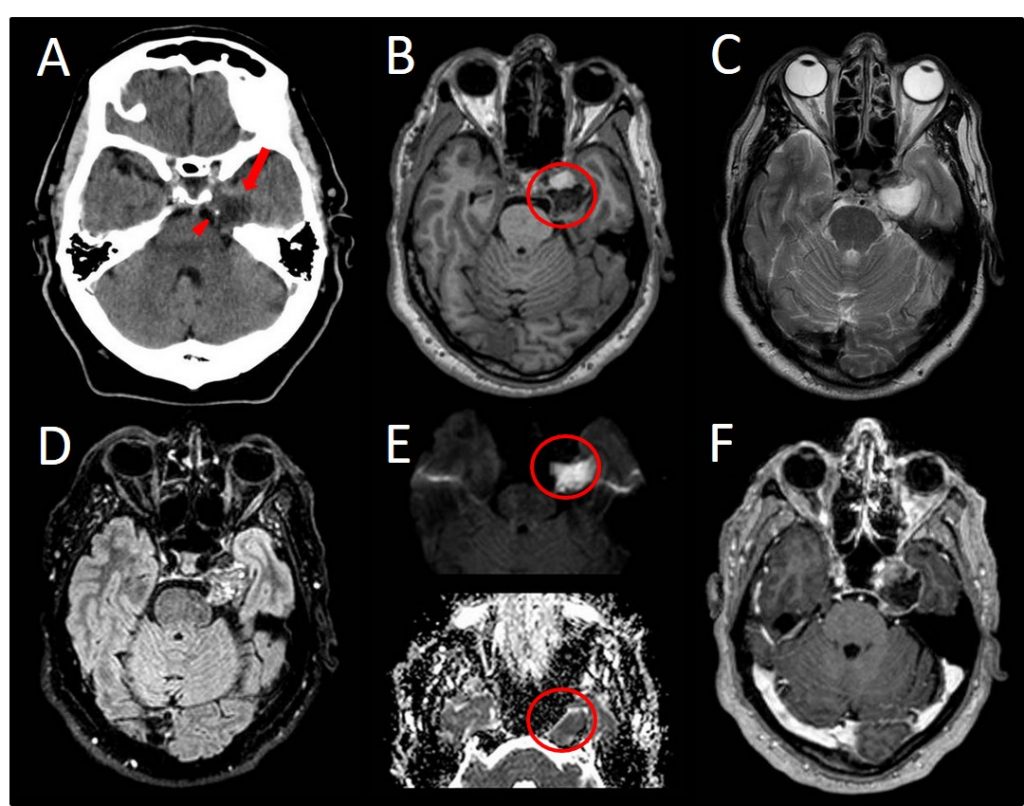

Varón de 65 años, consulta por cifras tensionales altas y cefalea. Se realiza TC objetivándose imagen sugestiva de LOE intracraneal (imagen A). Posteriormente RM.

A.- TC sin contraste, lesión hipodensa paraselar izquierda, de bordes bien definidos (flecha) con microcalcificaciones (cabeza de flecha).

B.- T1, lesión extraaxial de señal interna heterogénea, en seno cavernoso-cavum de Meckel izquierdo. Bien definida, íntimamente relacionada con porción cisternal del trigémino y que ejerce efecto masa sobre circunvolución parahipocampal izquierda sin comportamiento infiltrativo.

C.- T2, lesión hiperintensa con polo anterior de menor intensidad.

D.- FLAIR intensidad de señal heterogénea y polo anterior hipointenso.

E.- DIFUSIÓN y mapa ADC, existe una fuerte restricción a la difusión del polo posterior.

F.- CONTRASTE, la ligera captación de contraste periférica circunferencial.